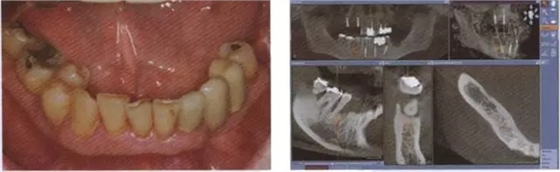

圖8 牙周病破壞了下合的牙齒系統(tǒng)

圖9 對牙周病破壞的下合員牙齒通過 CBCT數(shù)據(jù)進(jìn)行帶角度的種植規(guī)劃.